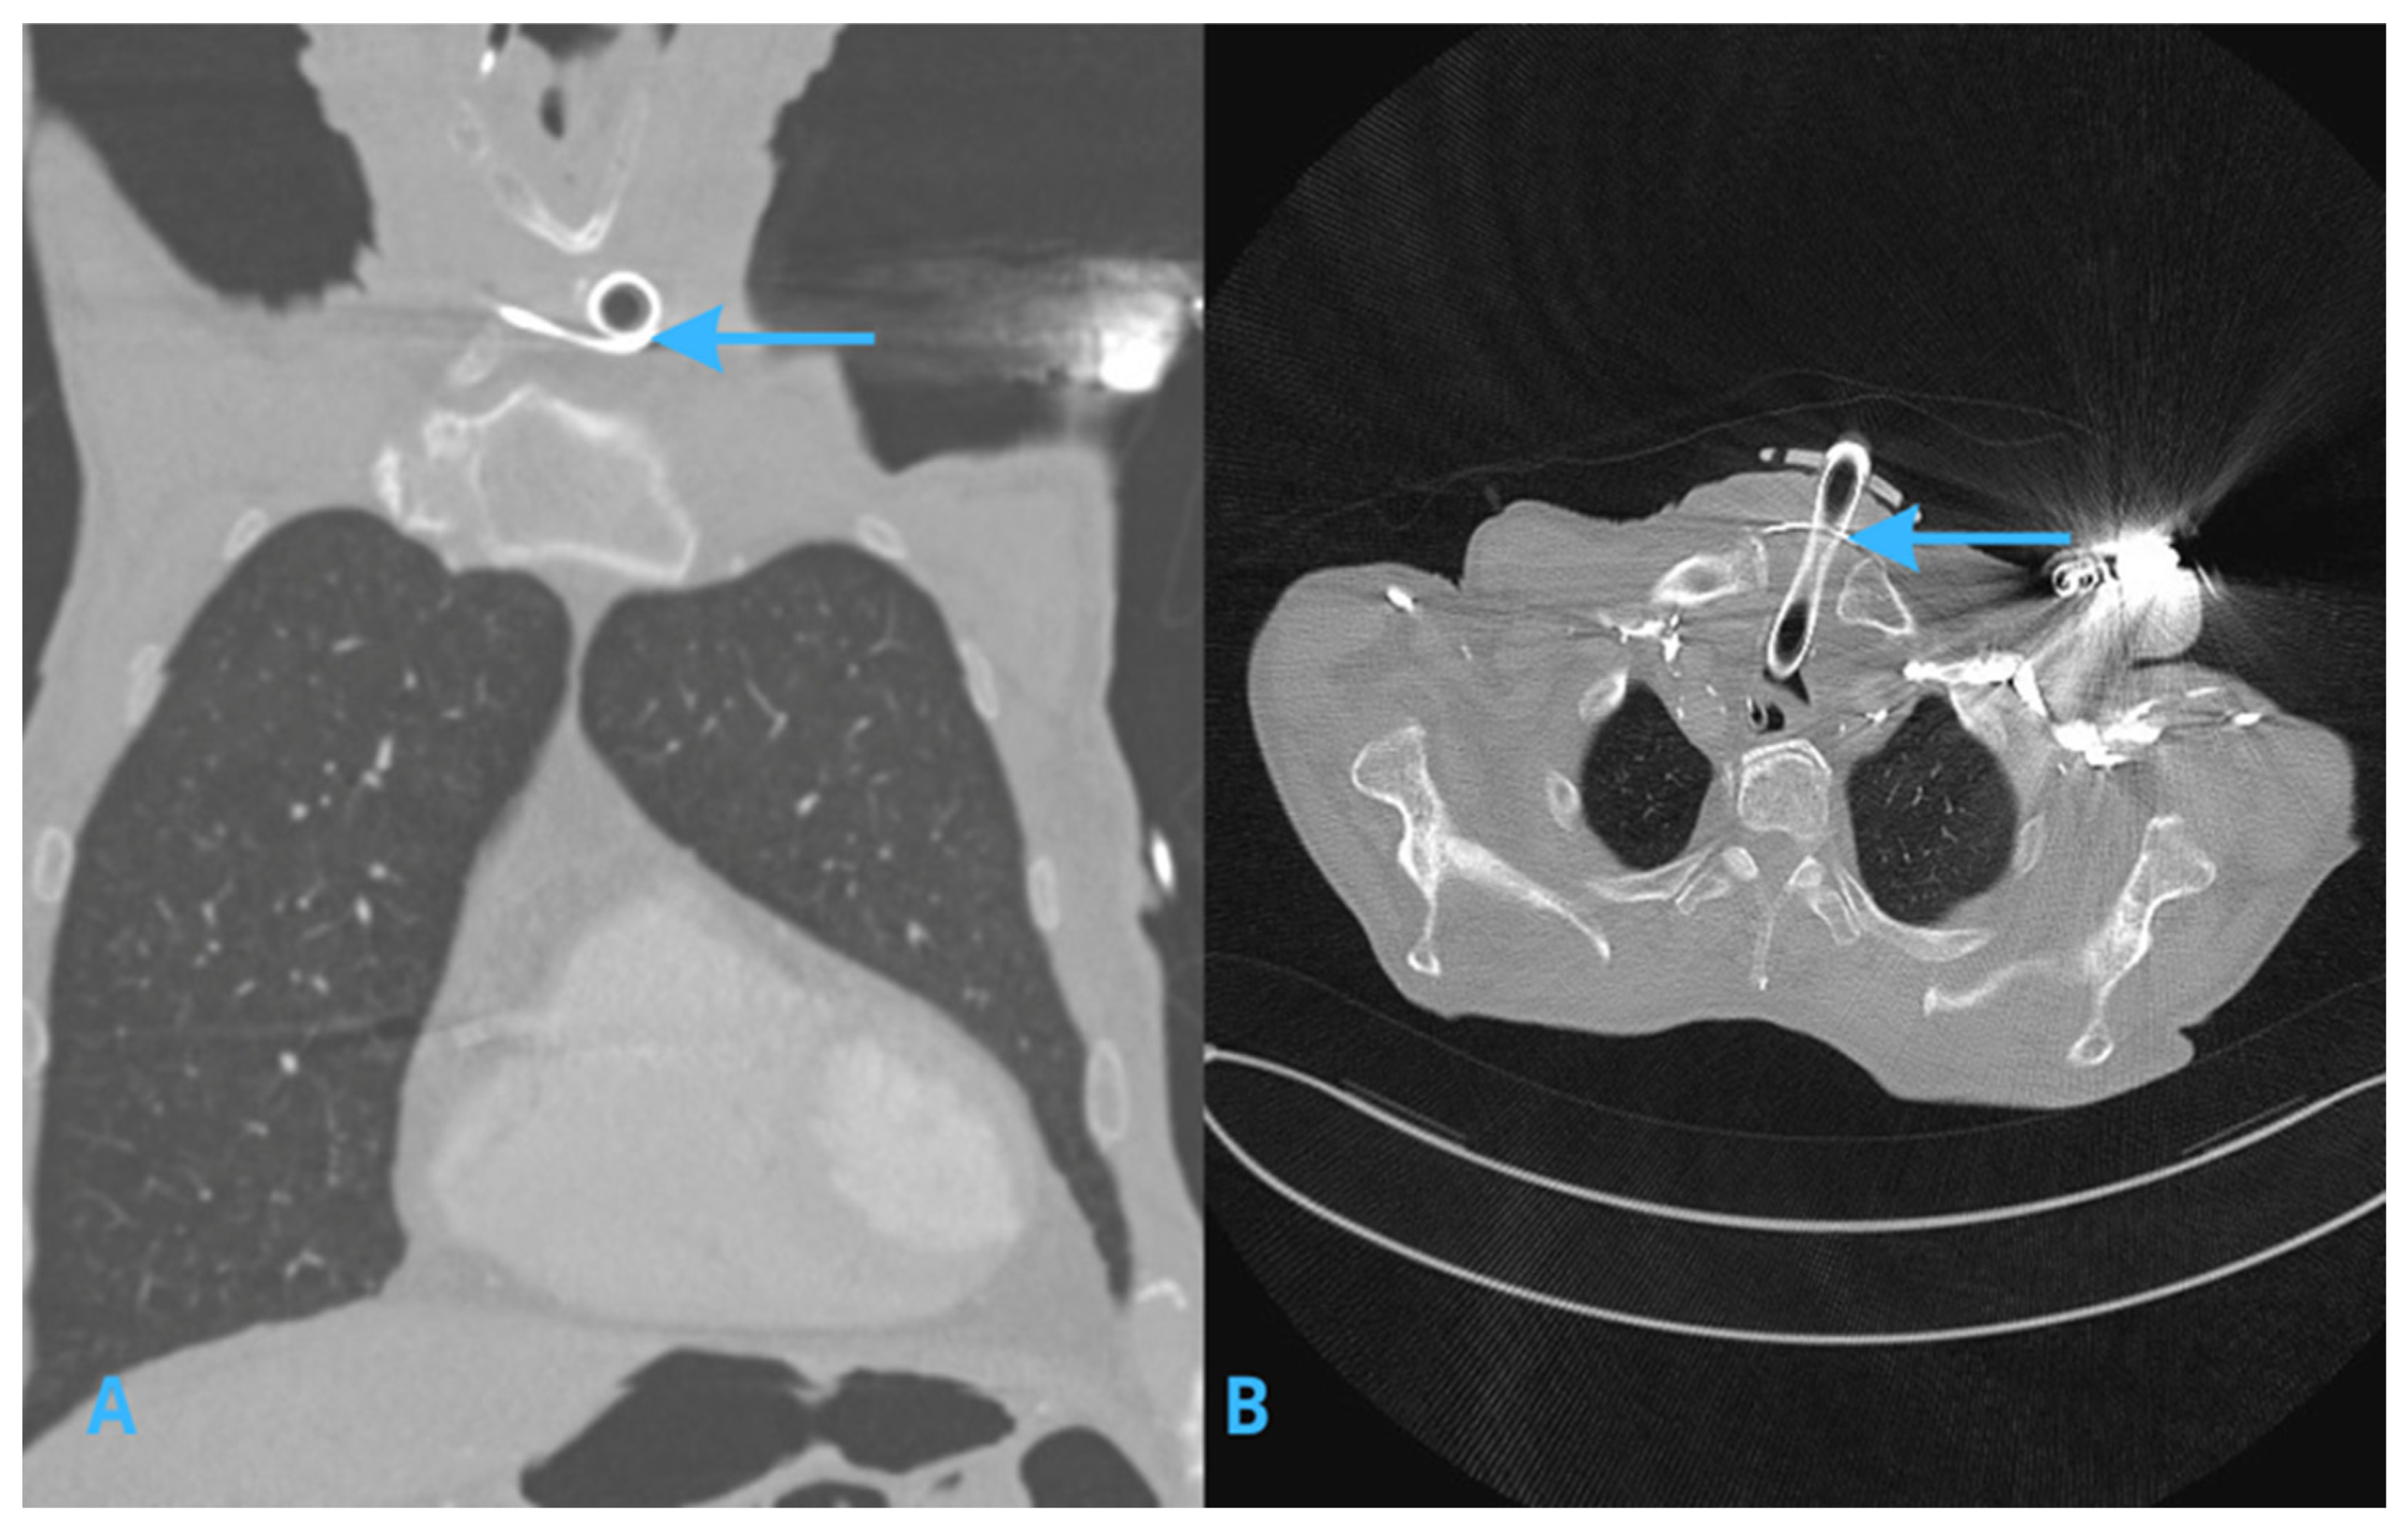

2.2. Computed Tomography (CT) Scans of the Chest